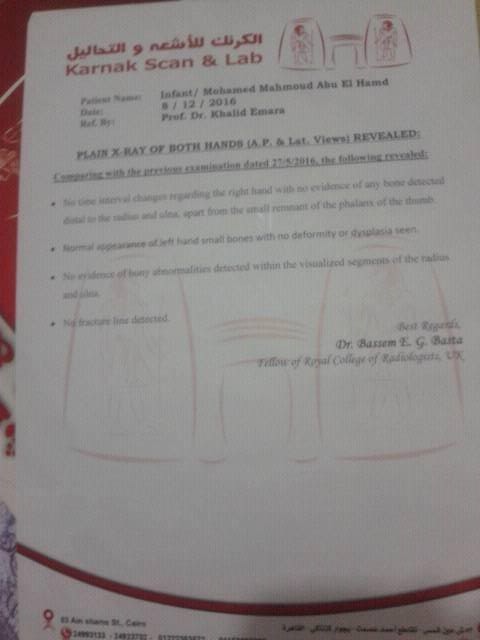

تحدثت والدة الطفل محمد محمود "صوت الأمة "عن حالة طفلها الذى لم يكمل عامه الأول قائلة :"ذهبت به للعديد من أطباء العظام لكن دون جدوى لم يستطيع أحد تشخيص حالة محمد حتى فسر أحد الأطباء الحالة بأنها بسبب تعرضى أثناء فترة الحمل لأشعة أو تناول أدوية معينة سببت التشوه ، أقترح على أحد الأطباء بتر 3 أصابع من الرجل لزرعها فى يده اليمنى وأنا لاأستطيع تشويه رجله لحل مشكلة يده "